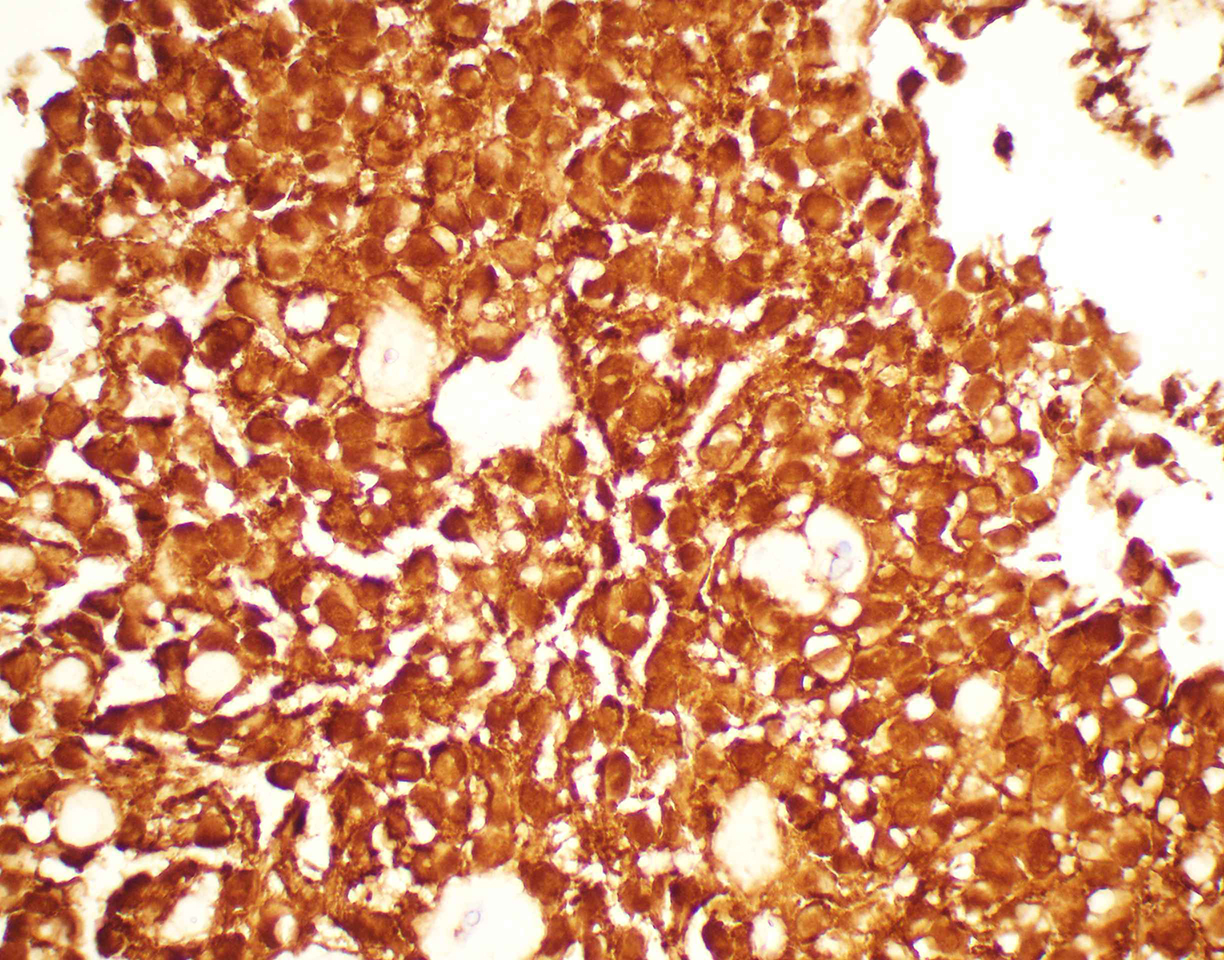

• Figure 5: Cell-block, Beta-catenin immunohistochemical stain,60x magnification

Point mutation in exon 3 of β-catenin gene (CTNNB1) is present in > 90% of SPNs. This genetic mutation results in the accumulation of β catenin in the cytoplasm and formation of a β-catenin Tcf/Lef complex, through which the WNT signaling pathway activates several oncogenic genes, such as MYC and cyclin D1. Rarely, mutations in the APC gene have been described.

Question 4: Correct answer is B. α1-Antitrypsin

The intracytoplasmic hyaline globules of SPN are PAS positive, diastase-resistant, and immunoreactive with α1-Antitrypsin.